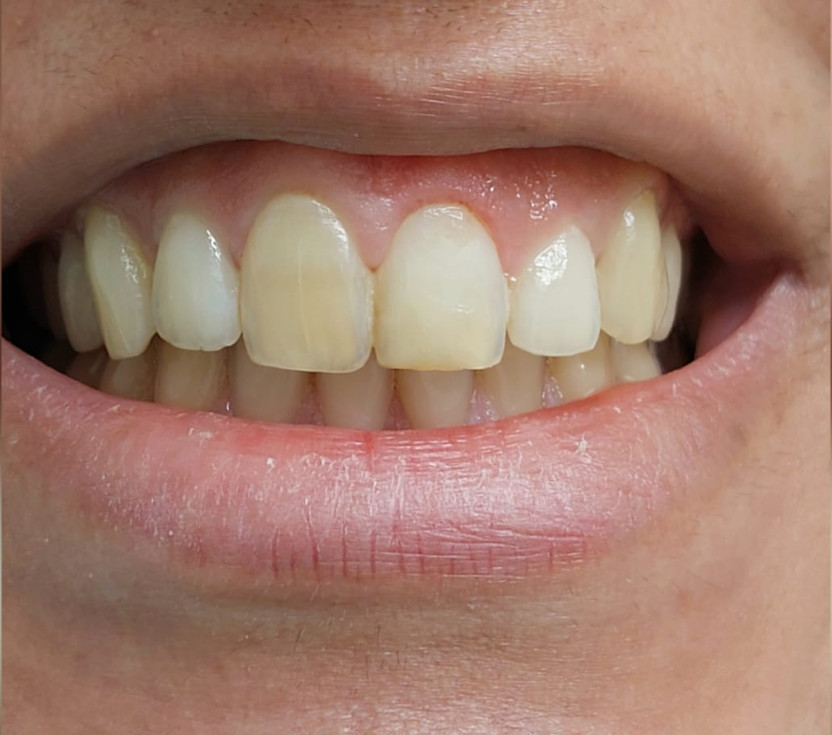

Caso Clinico

Restauri in composito

Il restauro di un dente cariato o fratturato si ottiene con il composito. È un materiale, in uso

da circa 45 anni, che diviene tutt’uno col dente.

È innocuo al dente e all’organismo. La gran parte dei restauri ha già superato i 35 anni.

Prima

Dopo